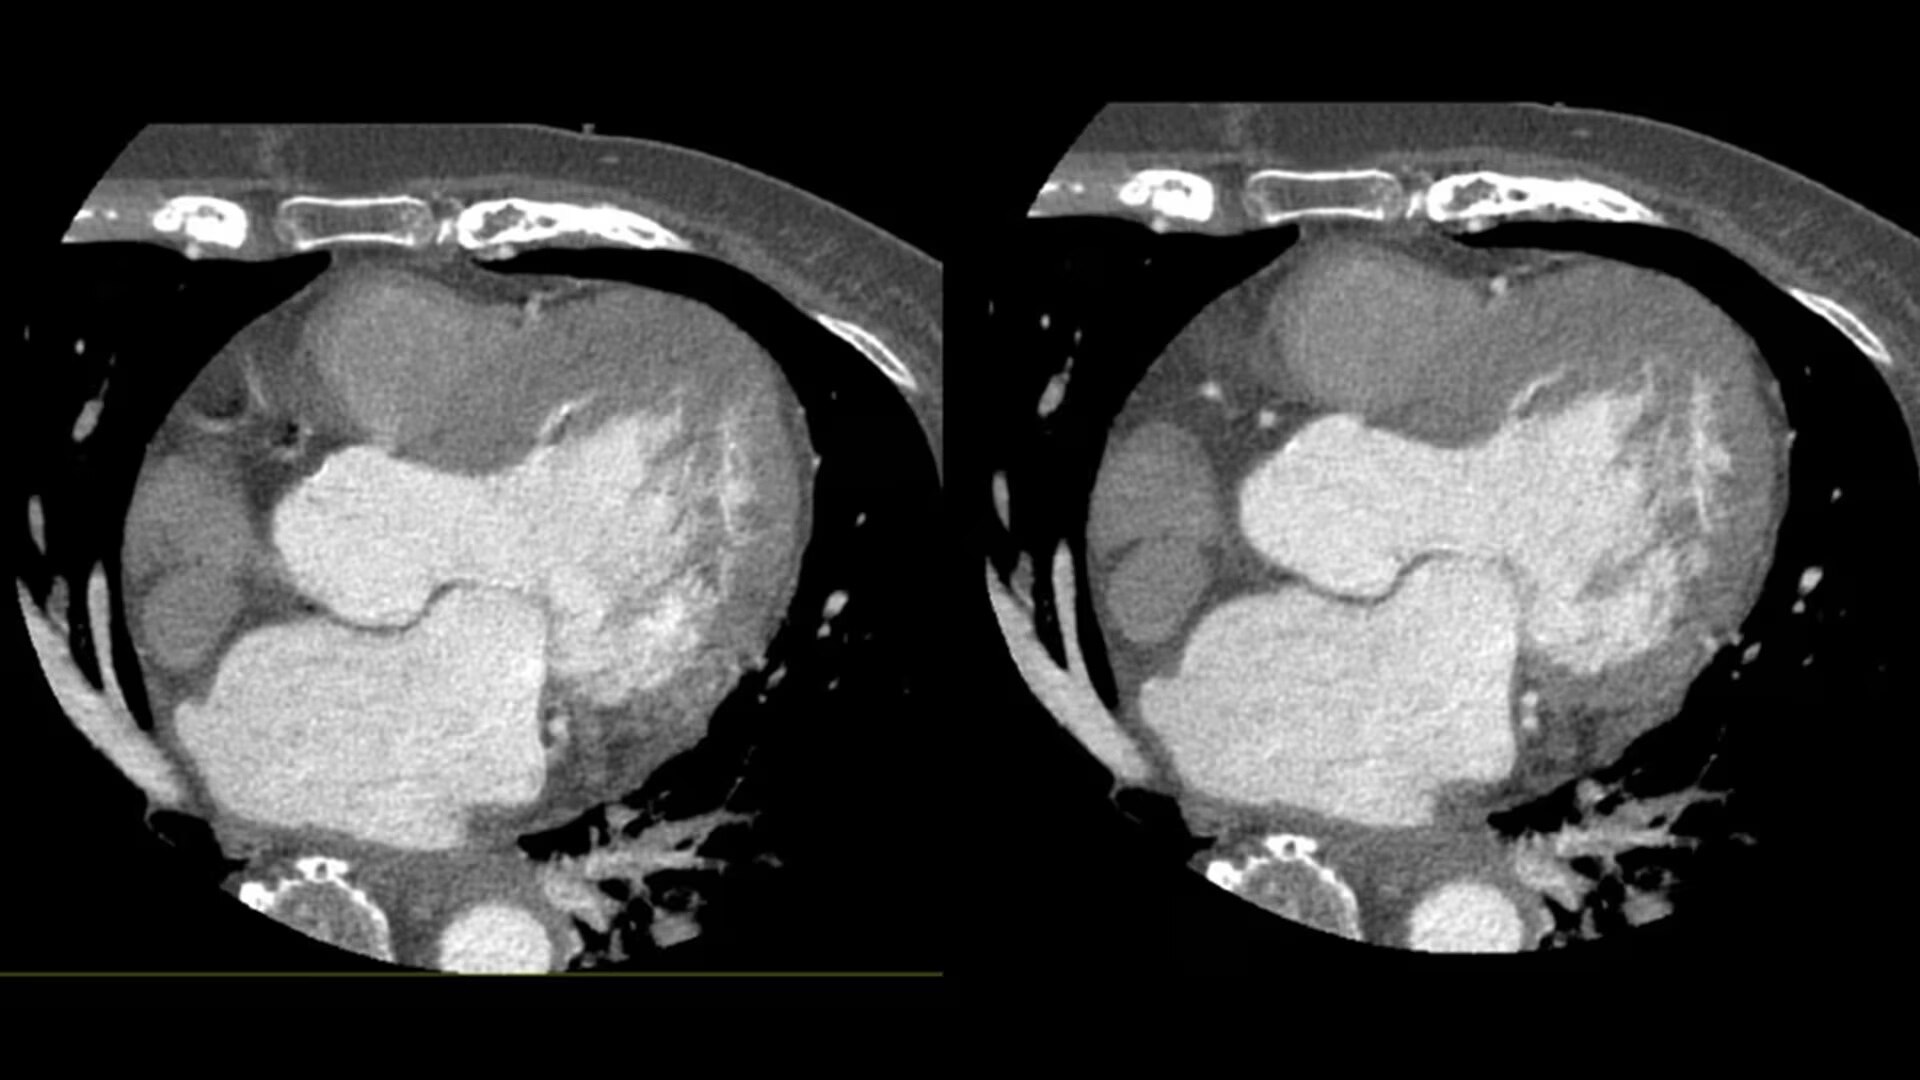

SnapShot Freeze 2

Intelligent and automated whole-heart motion correction for enhanced Cardiac CT imaging.

6x reduction in motion artifacts1

19.5 msec effective temporal resolution at 0.23s/rotation gantry speed2

Whole-heart motion correction